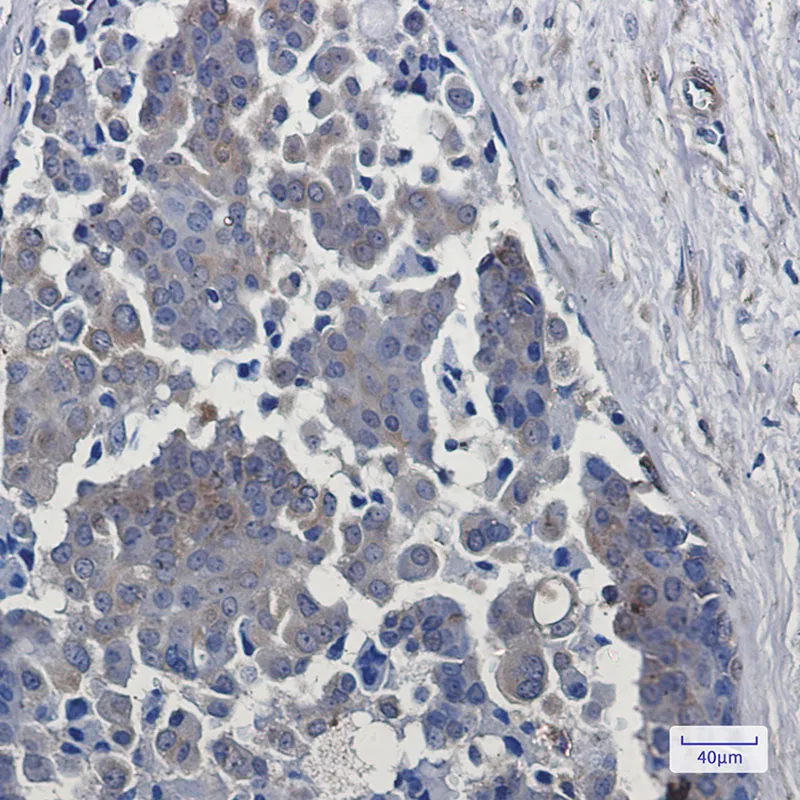

DYNLL1 Rabbit Monoclonal Antibody

Cat: AMRe01926

Size1:50μl Price1:$158

Size2:100μl Price2:$288

Size3:500μl Price3:$1200

Size2:100μl Price2:$288

Size3:500μl Price3:$1200